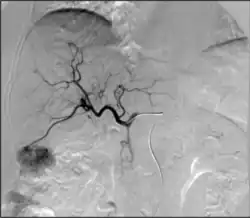

Ангиография: визуализация кровеносных сосудов для выявления аномалий с использованием различных контрастных веществ, включая йодированный контраст, вещества на основе гадолиния газ CO2 .[3]

ангиография артериита Такаясу